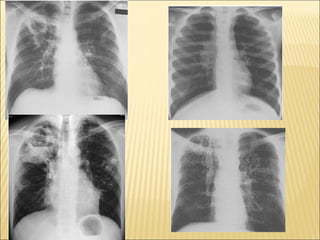

radiographic examination of the chest is usually the first diagnostic study undertaken, after the history and physical examination .  In primary tuberculosis, as a recent infection, is seen as a  middle or lower lung zone infiltrate , often associated with  ipsilateral hilar adenopathy  . Atelectasis may result from compression of airways by enlarged lymph nodes. If the primary process persists beyond the time when specific cell-mediated immunity develops,  cavitation may occur (so-called progressive primary tuberculosis).

Tuberculosis that develops many years after the original infection (endogenous reactivation) usually involves the upper lobes of one or both lungs.  Cavitation is common in this form of tuberculosis. The most frequent sites are the apical and posterior segments of the right upper lobe and the apical-posterior segment of the left upper lobe.  Healing of the tuberculous lesions usually results in development of a fibrotic scar with shrinkage of the lung parenchyma and, often, calcification. Involvement of the anterior segments alone is unusual. In the immunocompetent adult with tuberculosis, intrathoracic adenopathy is uncommon.  When the disease progresses, infected material may be spread via the airways (i.e., "bronchogenic" spread) into the lower portions of the involved lung or to the other lung. Erosion of a parenchymal focus of tuberculosis into a blood or lymph vessel may result in dissemination of the organism and a miliary pattern on the chest film .

the chest radiograph, although extremely valuable, cannot provide a definitive diagnosis of tuberculosis. Because of the:- 1-  Radiographic similarities among the other disorders  in the differential diagnosis, 2- And because of the  uncertainties in assessing disease activity  and in determining the reasons for progressive radiographic changes, careful microbiologic evaluation is always indicated. A nondiagnostic microbiologic evaluation should prompt a careful assessment for other causes of the radiographic abnormality.